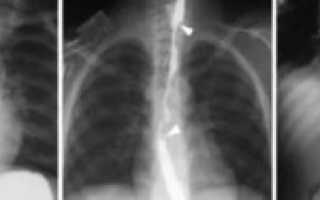

Рентгенологическое исследование позволяет обнаружить инородное тело, если оно рентгеноконтрастное, косвенные признаки аспирации нерентгеноконтрастного инородного тела (ателектаз, острая эмфизема сегмента, доли или целого легкого), маятникообразное смещение тени средостения при форсированном дыхании (при вдохе тень средостения смещается в сторону поражения, при выдохе — в здоровую сторону).

Особую сложность представляют случаи с неорганическими телами, ведь их не видно на стандартном рентген-снимке.

Однако даже тогда можно заметить косвенные признаки: ателектаз, эмфизему и очаговые изменения в легочной ткани.